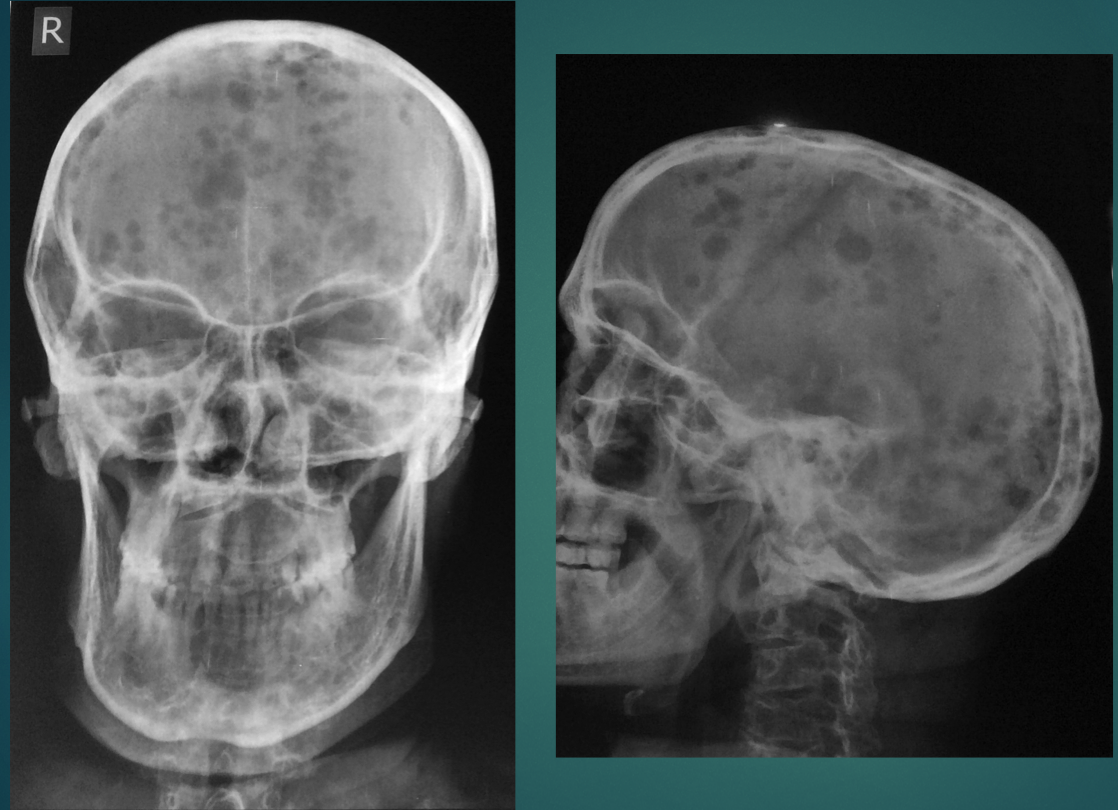

50 YO M. Weakness, fatigue, back pain.

Multiple, punched out, osteolytic lesions

think: MM or mets